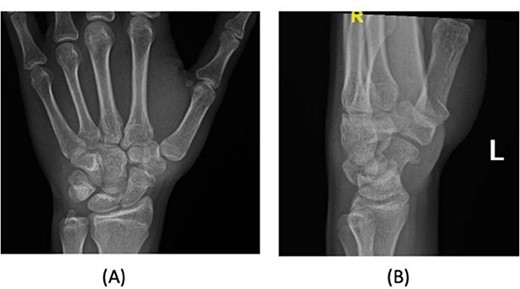

A 15-year-old boy, right handed, was not known to have any chronic medical illnesses. He presented to the emergency department (ED) with a history of severe left-wrist pain and swelling after falling from a height of 5–6 meters on an outstretched hand with the wrist in extension three hours prior to the ED presentation. The pain is mainly located in the left wrist’s dorsum and distal part of the forearm. Increasing pain with movement and relived with immobility. On examination, a normal-appearing wrist. No open wounds or lacerations, nor abrasions. There is no obvious deformity. There was mild swelling in the wrist. Tenderness over the dorsal radial wrist, including the anatomical snuff box. The range of motion was restricted due to pain. The neurovascular examination was normal. A plain radiograph in the ED showed a scaphoid tubercle fracture and a capital bone fracture. Initial radiographs are shown in Fig. 1). The patient was taken for computerized tomography (CT) to better define the extent of the injury (Fig. 2). A CT scan showed a displaced fracture of the capitate carpal bone, with an avulsion fracture at the distal tubercle of the scaphoid carpal bone, with extension to the articular surface. In addition to perilunate fracture, the rest of the carpal bone’s alignment is maintained. The patient was shifted to the operating room for open reduction and k-wire fixation of the scaphoid and capitate fracture of the left hand. Under general anesthesia, a tourniquet was applied. The incision was over the dorsal aspect of the left wrist, proceeding with the wrist capsule opening. The fracture was fixated with two Kirschner wires. Alignment was assured intraoperatively with an x-ray (Fig. 3). Plain radiographs post-fixation showed intact alignment. Postoperatively, the wrist was immobilized in a long-arm splint. The Kirschner wires and the protected splint were removed at 5 and 8 weeks, respectively. Immediately afterward, physiotherapy started. A few months following surgery, the site of the fracture healed radiologically. The patient had no pain, and the range of motion was acceptable after a period of physiotherapy. Figure 4 demonstrates a medical illustration of a scaphocapitate fracture.

Initial injury posteroanterior and lateral radiograph demonstrating left wrist.